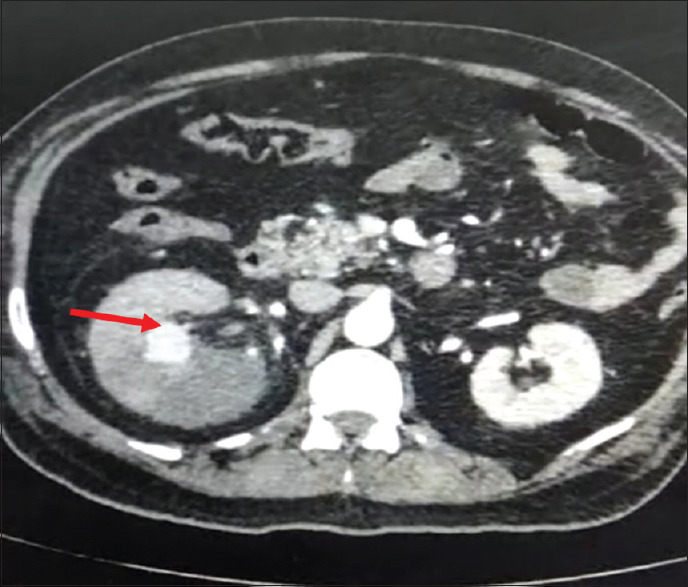

本病例报告讨论了 COVID-19 康复后出现的一种罕见的严重并发症--导致右肾动脉假性动脉瘤的肾粘液瘤病。一名曾接受过 COVID-19 治疗的 59 岁患者出现干咳、侧腹疼痛和血尿。他被诊断为肾动脉假性动脉瘤伴肾粘液瘤病。成功的治疗包括紧急血管栓塞术、全身用脂质体两性霉素 B 以及稳定后的根治性肾切除术。该病例强调了COVID-19后警惕性随访的重要性,尤其是对接受类固醇治疗的患者,并强调了采用多学科方法及时诊断和有效治疗粘液瘤病相关并发症的必要性。

This case report discusses a rare and severe complication of COVID-19 recovery - renal mucormycosis leading to right renal artery pseudoaneurysm. A 59-year-old patient, previously treated for COVID-19, presented with dry cough, flank pain, and hematuria. He was diagnosed with renal artery pseudoaneurysm with renal mucormycosis. Successful management included urgent angioembolization, systemic liposomal amphotericin B, and subsequent radical nephrectomy post-stabilization. The case underscores the importance of vigilant post-COVID-19 follow-up, particularly in patients treated with steroids, and highlights the need for a multidisciplinary approach for timely diagnosis and effective management of mucormycosis related complications.